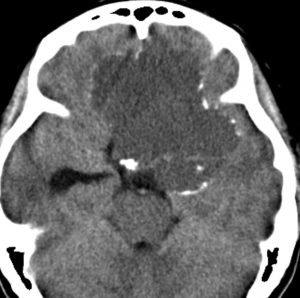

この子の症状は頭痛だけ。両親はなぜ気づかなかったのかと疑問を持ちますが,巨大になるまで症状が出ないこともあるのです。左のCTで腫瘍の周囲にバラバラと白い点状の石灰化があるので診断できます。左の視床下部から発生したクラニオでした。開頭手術しますが超高難易度です,怖いです (┯_┯) 複数回開頭手術になりましたが結果的に全摘出できています (by Dr 山本哲哉)。